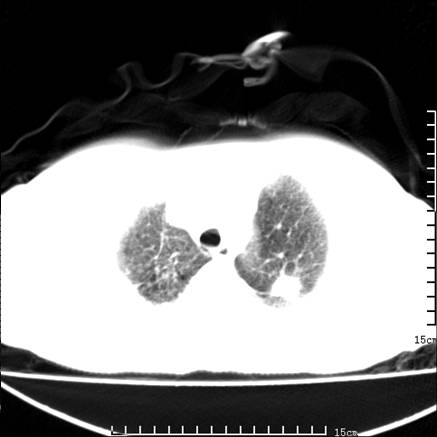

女,王某,58岁,咳嗽三个月余,基层医院二个月前诊为肺结核,用抗结核药二个月无明显疗效。

心包积液致肺瘀血.右侧周围型肺癌伴肺内转移,中间裂积液,叶间胸膜肥厚.右上肺大泡,右侧胸膜肥厚.

双肺继发型tb,心功能不全并肺淤血、心包、双侧叶间裂积液,肺大泡,右下胸膜肥厚钙化。